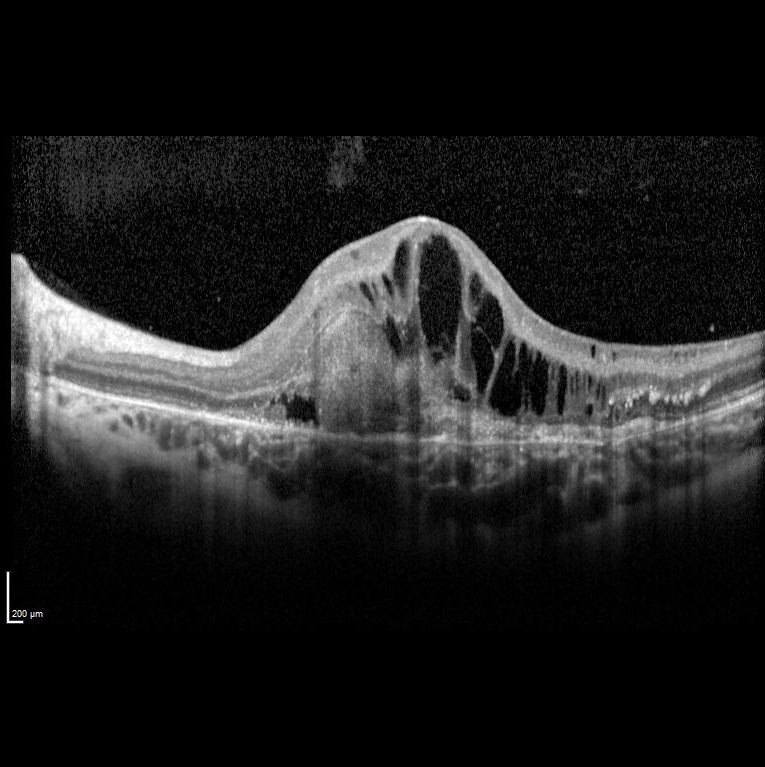

Sol gözde bir haftadır görme azlığı şikayeti başlayan ve görme keskinliği 5 mps düzeyinde olan 15 yaşındaki kadın hasta retina kliniğimize refere edilmiştir. Hastanın renkli fundus ve optik koherens tomografi görüntülerini görmektesiniz. Hastanın doğumunda bir enfeksiyon öyküsü vardır. Sistemik bir hastalığı yoktur. Bu bulgulara göre tanınız nedir? Lütfen cevabınızı aşağıya yazınız.

Bu ay size sol gözde bir haftadır görme azlığı şikayeti başlayan ve görme keskinliği 5 mps seviyesinde olan 15 yaşındaki kadın hastanın renkli fundus ve optik koherens tomografi görüntüleri eşliğinde tanısını sormuştuk.

Tanı: Rubella Retinopati ve maküla/koroid neovaskülarizasyonu’dur.

Konjenital rubella vakaları genellikle katarakt, mikroftalmi, glokom veya pigmenter retinopati ile oftalmoloji bölümüne başvurur. Görme kaybı genellikle katarakt veya eşlik eden mikroftalmi ve nistagmus nedeniyle olur. Pigmenter retinopati tek başına genellikle görme kaybına yol açmaz. Makuladaki retinal tabakaların kronik atrofisine bağlı pigmenter retinopati ile ilişkili olarak gelişen maküla/koroid neovaskülarizasyonu görme kaybına yol açar.

Literatürde rubella retinopatisine bağlı maküla/koroid neovaskülarizasyonu hakkında az sayıda rapor bulunmaktadır. Çalışmalar, kızamıkçık retinopatisine bağlı maküla/koroid neovaskülarizasyonunun yedavi edilmez ise tipik olarak kötü bir görsel prognoza sahip olduğunu göstermiştir. Birkaç istisna dışında, hastalarda diskiform skarlaşma gelişmiş ve görme keskinliği önemli ölçüde azalmıştır.

Literatürde fotodinamik tedavi (PDT) ve anti-VEGF ajanları gibi birkaç tedavi seçeneği tanımlanmıştır. PDT'nin etkili bir tedavi seçeneği olduğu ve neovasküler membranın involüsyonuna, subretinal kanamanın çözülmesine ve görme keskinliğinde iyileşmeye yol açtığı bulunmuştur. Anti-VEGF tedavisi, başka bir seçenektir. Yaygın olarak kullanılan anti-VEGF ajanları bevacizumab, ranibizumab ve aflibercepttir. Anti-VEGF ile maküla/koroid neovaskülarizasyonu'nun önemli ölçüde düzeldiği rapor edilmiştir. Olgumuzda da bu durum izlenmiştir.